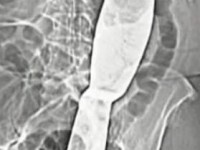

ORGAN ZA NEČIJI SPAS

Doniranje bubrega ne skraćuje životni vijek

SVJETSKI DAN BUBREGA

Gotovo polovici dijabetičara prijete oštećenja ili zatajenja bubrega